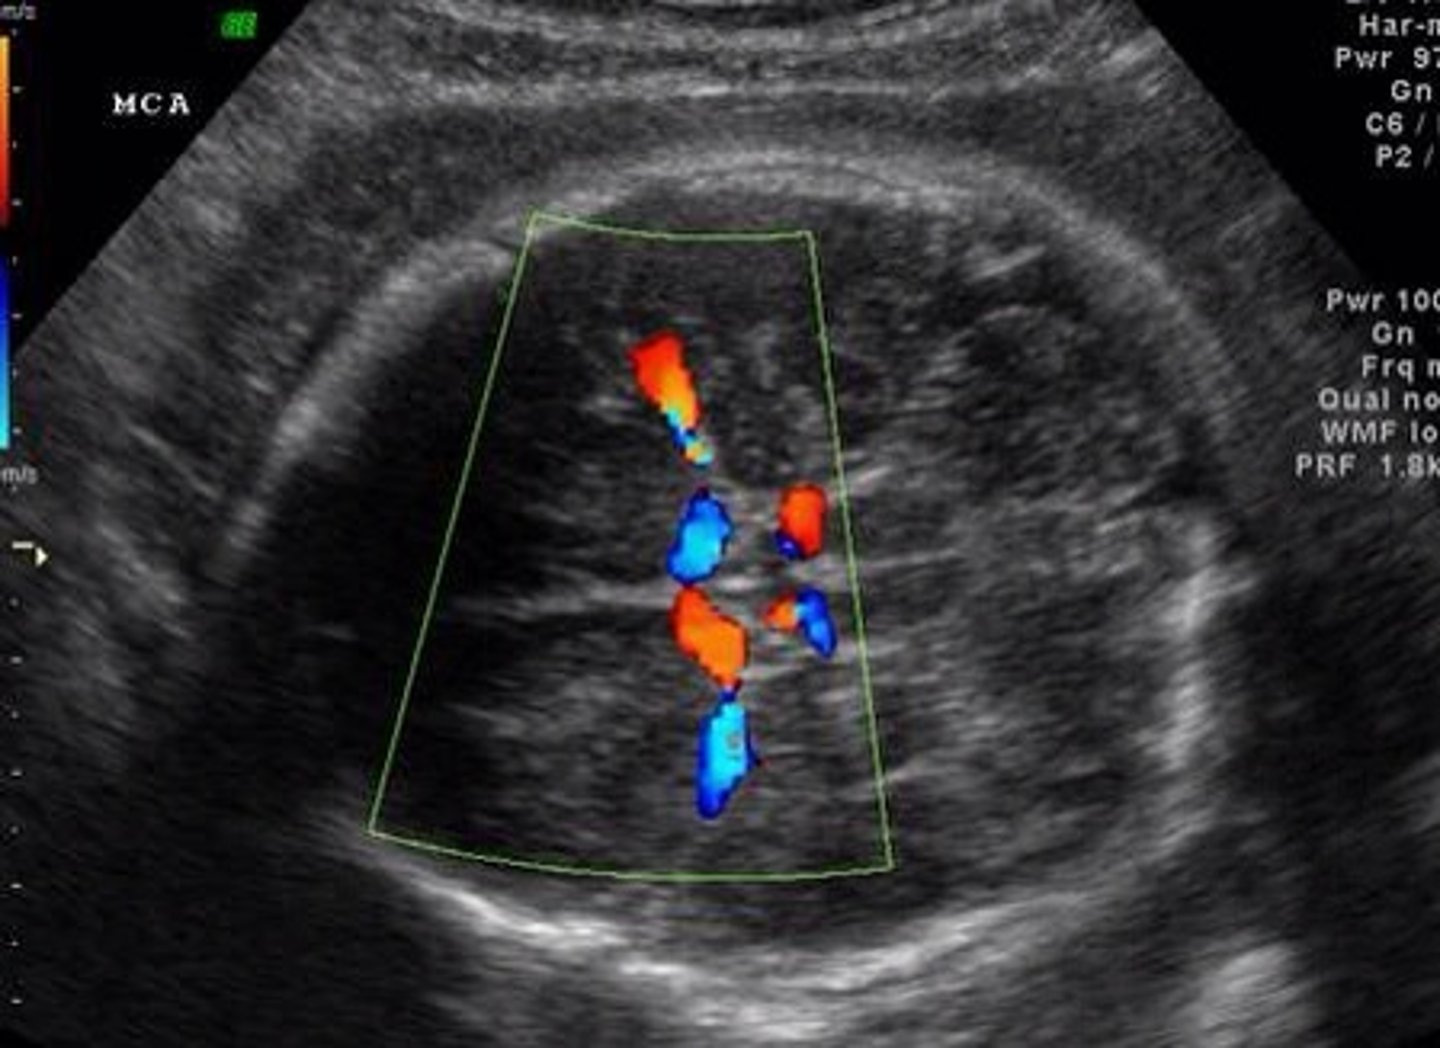

What are the 2 things Real-Time Imaging (doppler mode) can do?

Can measure movement

Ex. heartbeat

Can assess direction of flow

valve regurgitation